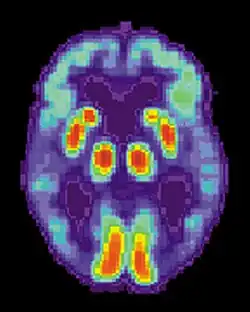

O diagnóstico da doença de Alzheimer é geralmente baseado na observação comportamental e no historial clínico da pessoa e respetivos familiares. O diagnóstico é apoiado pela presença de características neurológicas e neuropsicológicas e pela exclusão de outras hipóteses.[109][110] A exclusão de outras patologias cerebrais ou outros subtipos de demência pode ser auxiliada por diversas técnicas de imagiologia médica, como a tomografia computadorizada (TAC), ressonância magnética (IRM), tomografia computorizada por emissão de fotão único (SPECT) ou tomografia por emissão de positrões (TEP).[111] Estas técnicas permitem ainda prever a evolução de estádios pródromos (défice cognitivo ligeiro) para a doença de Alzheimer.[112]

Meios de diagnóstico

Em pessoas já com demência, a tomografia computorizada por emissão de fotão único (SPECT) aparenta ser superior a distinguir a doença de Alzheimer de outras causas possíveis, em comparação com os convencionais testes mentais e análise do histórico clínico.[279] Os avanços nesta área levaram a que fossem propostos novos critérios de diagnóstico.[23][116] A ressonância magnética volumétrica permite detetar alterações no tamanho das regiões do cérebro. A medição das regiões que sofrem atrofia durante a evolução da doença de Alzheimer é promissora enquanto indicador de diagnóstico e pode vir a ser menos dispendiosa do que outros métodos imagiológicos atualmente em estudo.[280] Embora o composto B de Pittsburgh ainda se encontre em investigação, um radiofármaco semelhante para tomografia por emissão de positrões, denominado florbetapir, foi recentemente aprovado nos Estados Unidos para o diagnóstico de Alzheimer.[281] Em 2019 foi desenvolvido um algoritmo que permite estimar o risco de desenvolver demência precoce. Este algoritmo é potencialmente capaz de prever o risco de novos diagnósticos de demência até oito anos mais cedo.[282]